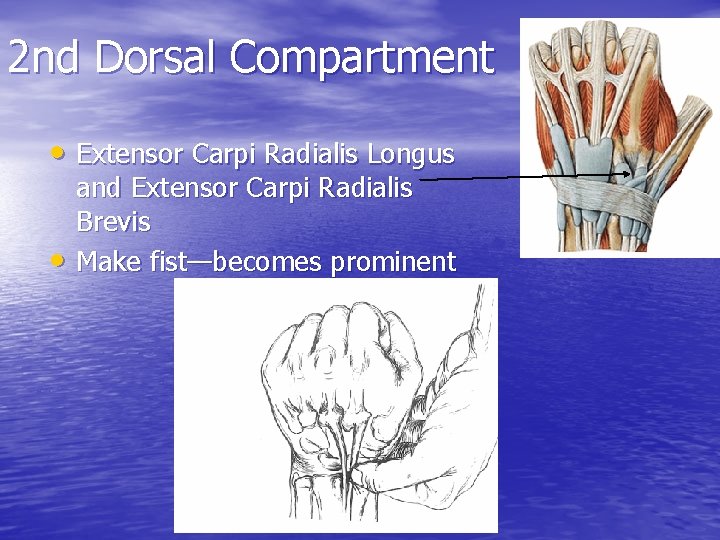

2 nd Dorsal Compartment • Extensor Carpi Radialis Longus • and Extensor Carpi Radialis Brevis Make fist—becomes prominent